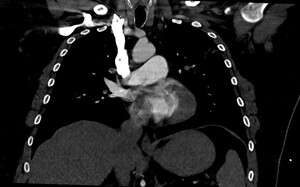

This prompted a re-evaluation of the initial CTPA by a specialist cardiothoracic radiologist. The following figures show selected images from the CTPA. Figure 1 is an axial slice demonstrating the already known bilateral filling defects within branches of the pulmonary arterial system, consistent with PEs (stars).